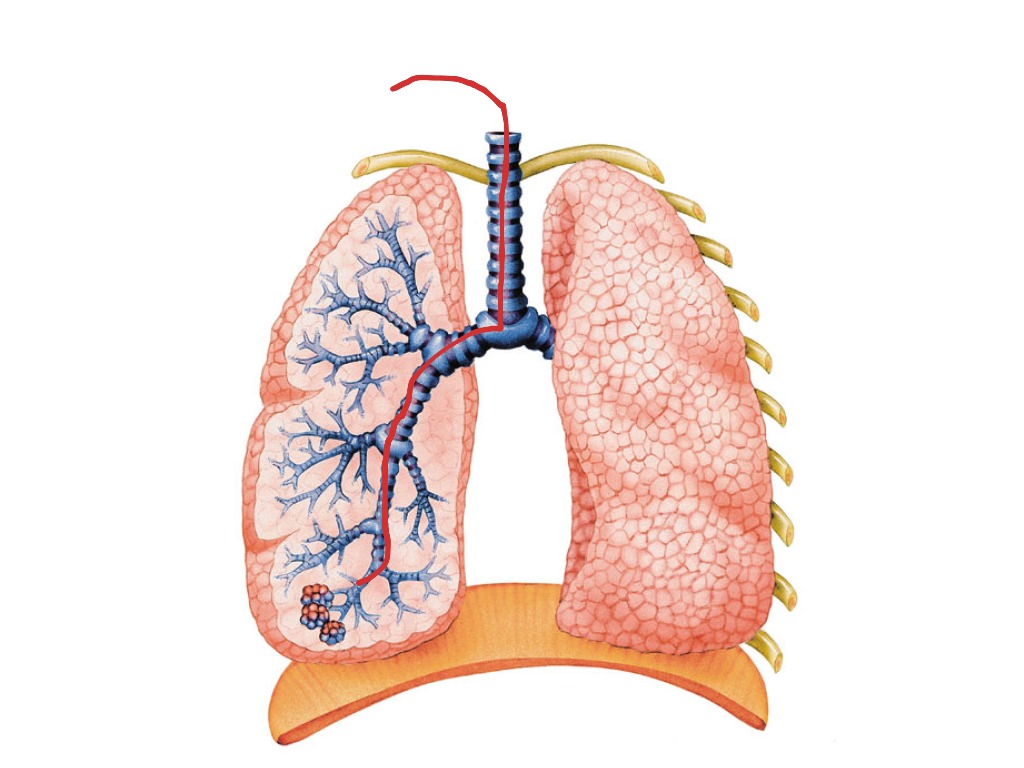

Лёгкие человека: Учебные картинки для детей